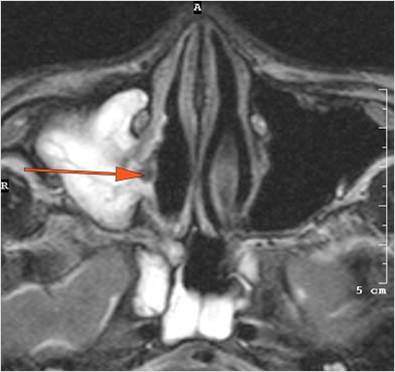

The superior and/or inferior ophthalmic veins are dilated or thrombosed. [Yes/No]

There is evidence of thrombus, thrombophlebitis or other occlusive or inflammatory process of the cavernous sinus. [Yes/No]

Findings are consistent with the clinical diagnosis of acute or subacute sinusitis complicated by orbital venous, cavernous sinus or other venous or dural sinus thrombosis.